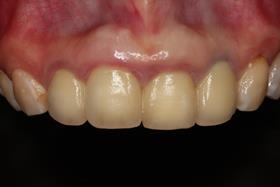

假牙完成後,植牙與自然牙,真假難辨;病患恢復自信的笑容。